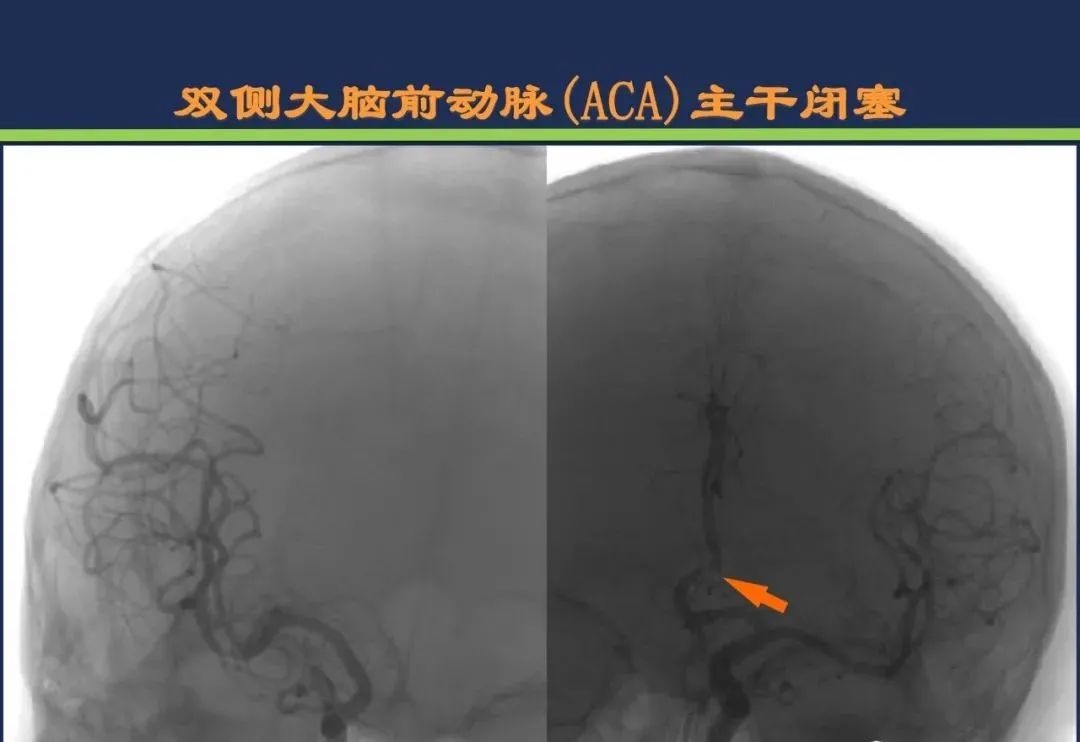

大脑前动脉